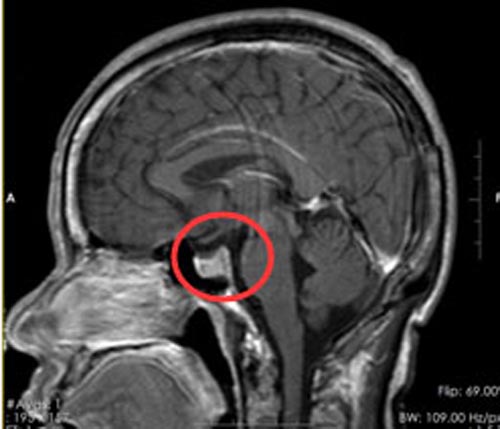

李女士从10年前开始四肢逐渐变得粗大,当时不以为然,直到最近出现了眼睛看东西模糊、头痛,才来到广东三九脑科医院,脑部影像检查后诊断为:鞍区占位:考虑垂体瘤。

既兴奋又疑惑的李女士接受了“内镜经鼻蝶鞍区占位切除术”,手术非常顺利,手术效果大大超出了她的预期,不但看不出有伤疤,头痛症状也消失了。

▲手术前